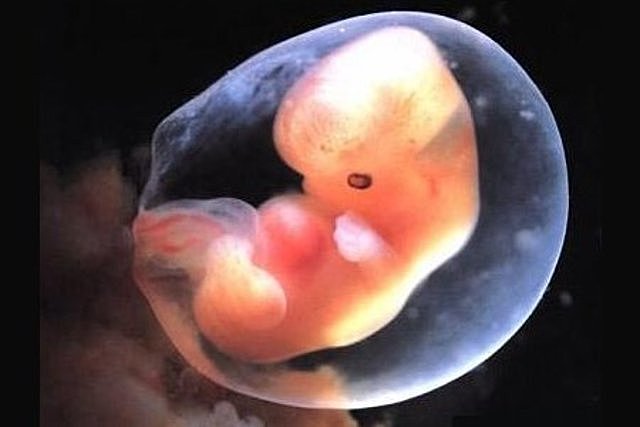

• Quinta semana

Quinta semana

En esta semana el embrión tiene apenas tres semanas de edad (correspondientes a la semana 5 de embarazo) y mide alrededor de un milímetro de ancho y cuatro-cinco milímetros de largo. Ya empieza a tener partes más diferenciadas en su característica forma de “C”